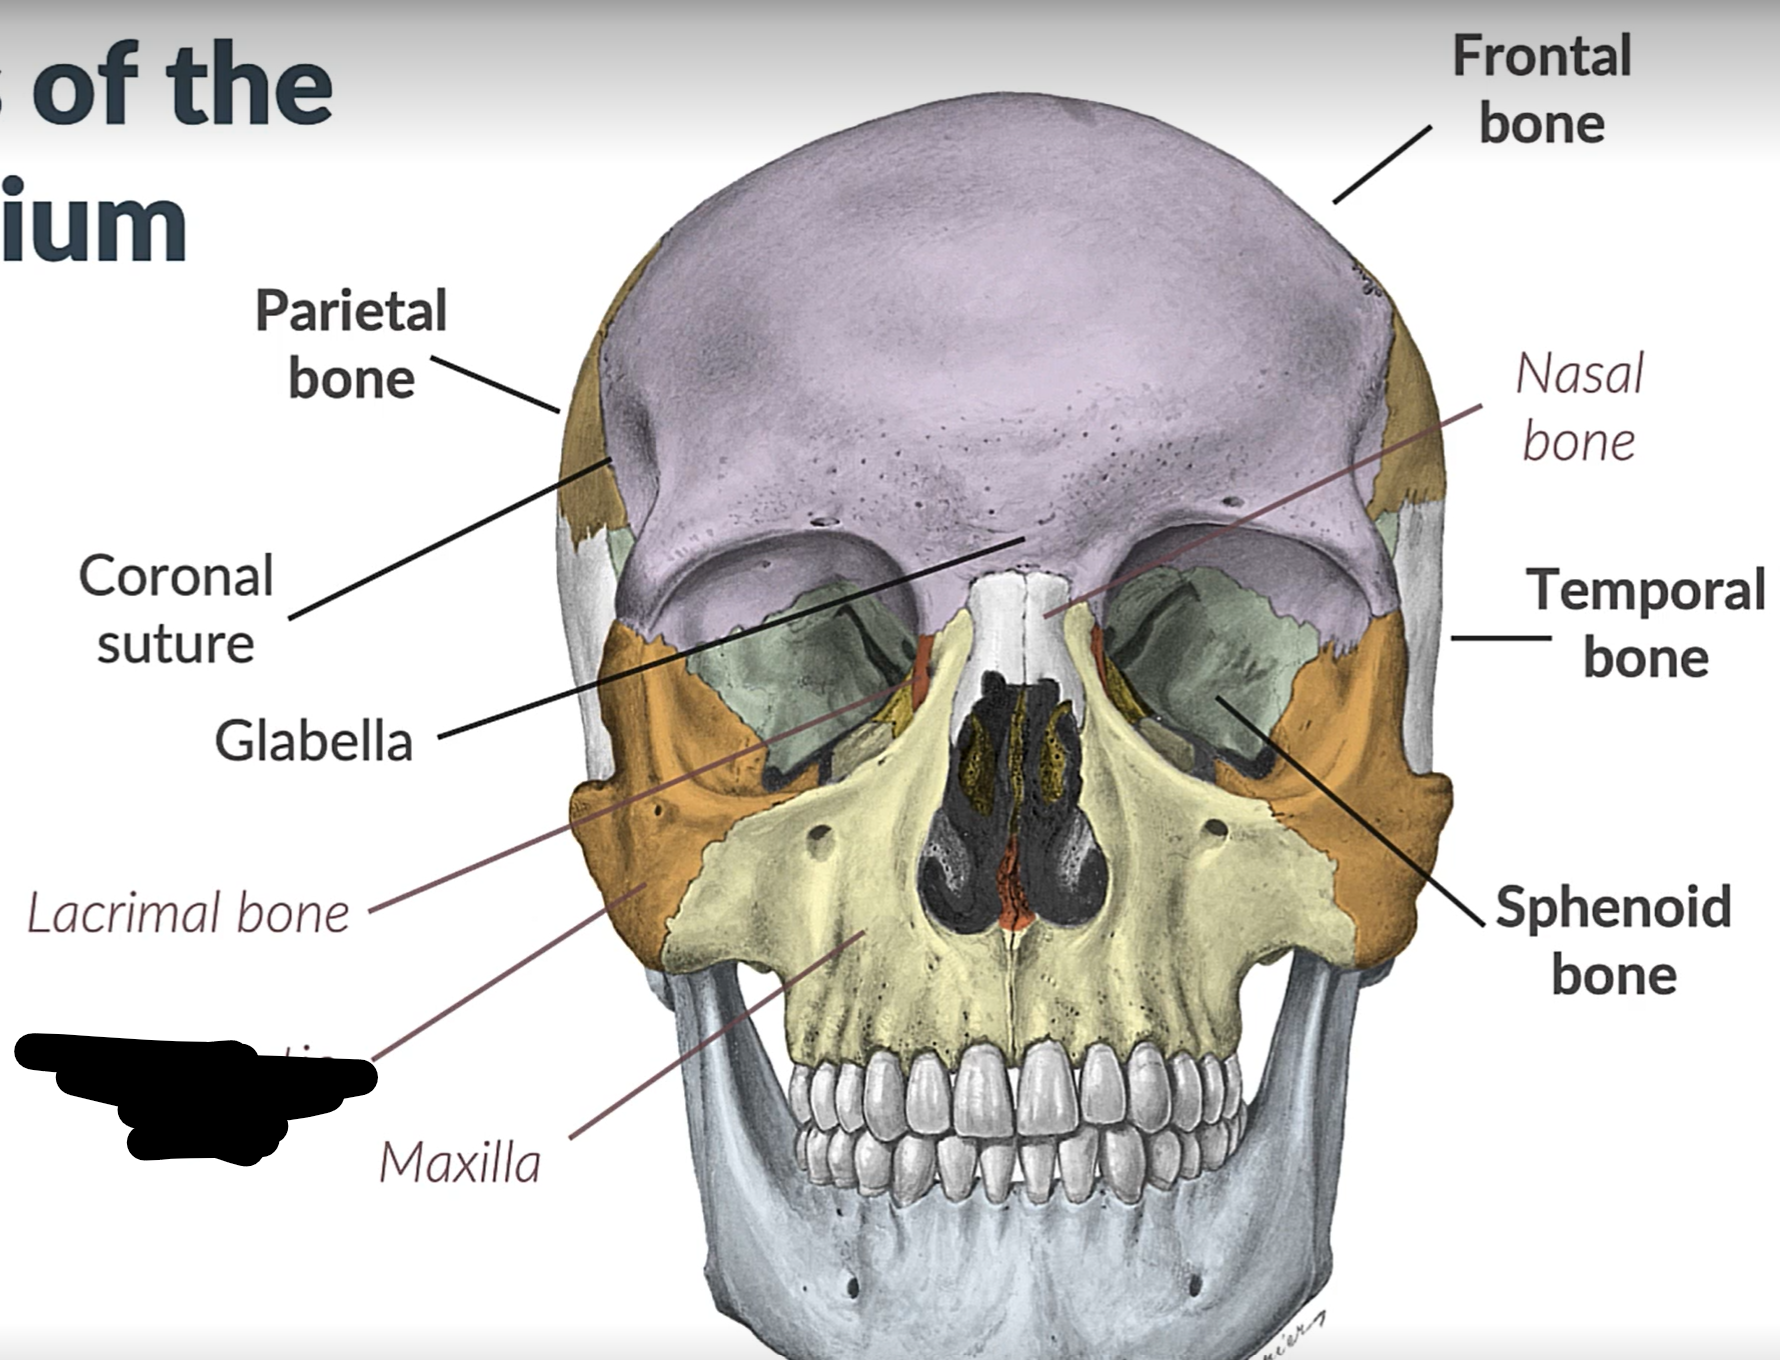

Parietal bone

Frontal bone

Temporal bone

Sphenoid bone

Zygomatic bone

Lacrimal bone

Coronal suture

Maxilla